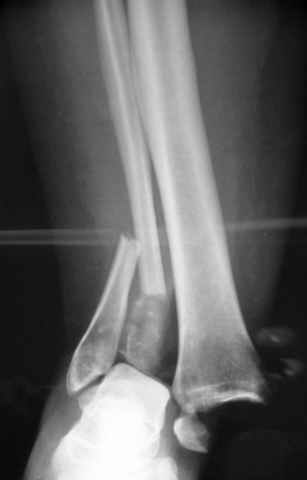

Еще, кстати, о фиксации лодыжки, если уж непременно хочется ее отдельно стабилизировать - при таком характере перелома замечательно должен сработать предложенный проф. Лазаревым с соратниками способ фиксации напряженной V-образной спицей. Опять же, открытая репозиция не нужна, мы делаем непрямую репозицию именно аппаратом. В приложении пример, там перелом малоберцовой куда менее поперечный, чем в данном случае, но все равно получилось закрыто без пластинки.

A propos fibular fixation if one is eager to stabilize it separately. In the fracture pattern a way of closed fixation by V-shaped stressed wire (advanced by colleagues from Moscow, prof. Lazarev A.F. et al.) must be excellent. We use indirect closed reduction by the external fixator. Example attached, that fibular fracture is even more suitable for plating but the wire did the job.